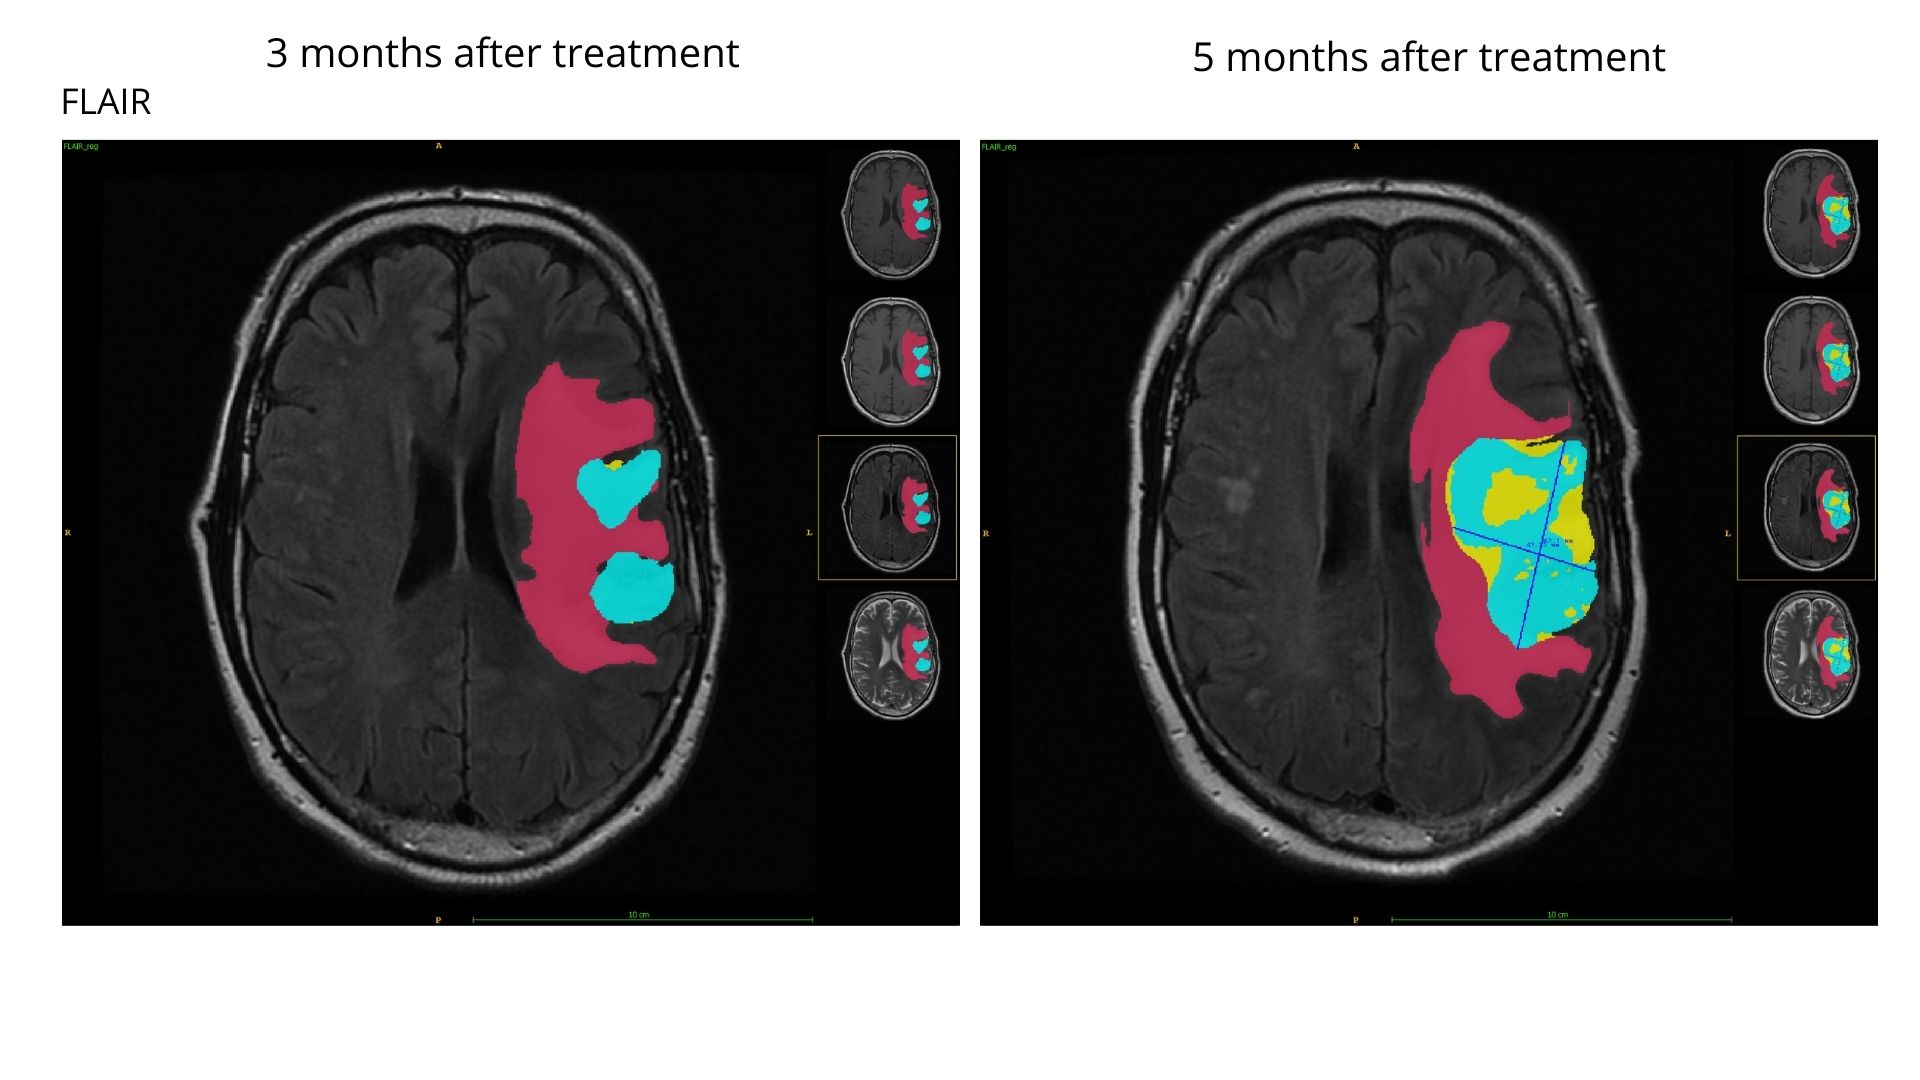

Brain tumor segmentation: progression

In this case, our model showed a doubled tumor burden in just 2 months between scans for this patient. Two separate enhancing tumor regions have grown and merged into one big lesion. It is reflected in RANO measurement marked in the later scan (RANO for the earlier scan was measured on a different slice). In sum, all the subregions have expanded what confirms the rapid tumor progression.

Edema: 82 cm3

Enhancing (ET): 20 cm3

Necrosis: 2 cm3

Tumor progression

RANO +100%

ET volume +85%

Edema: 136 cm3

Enhancing (ET): 36 cm3

Necrosis: 20 cm3